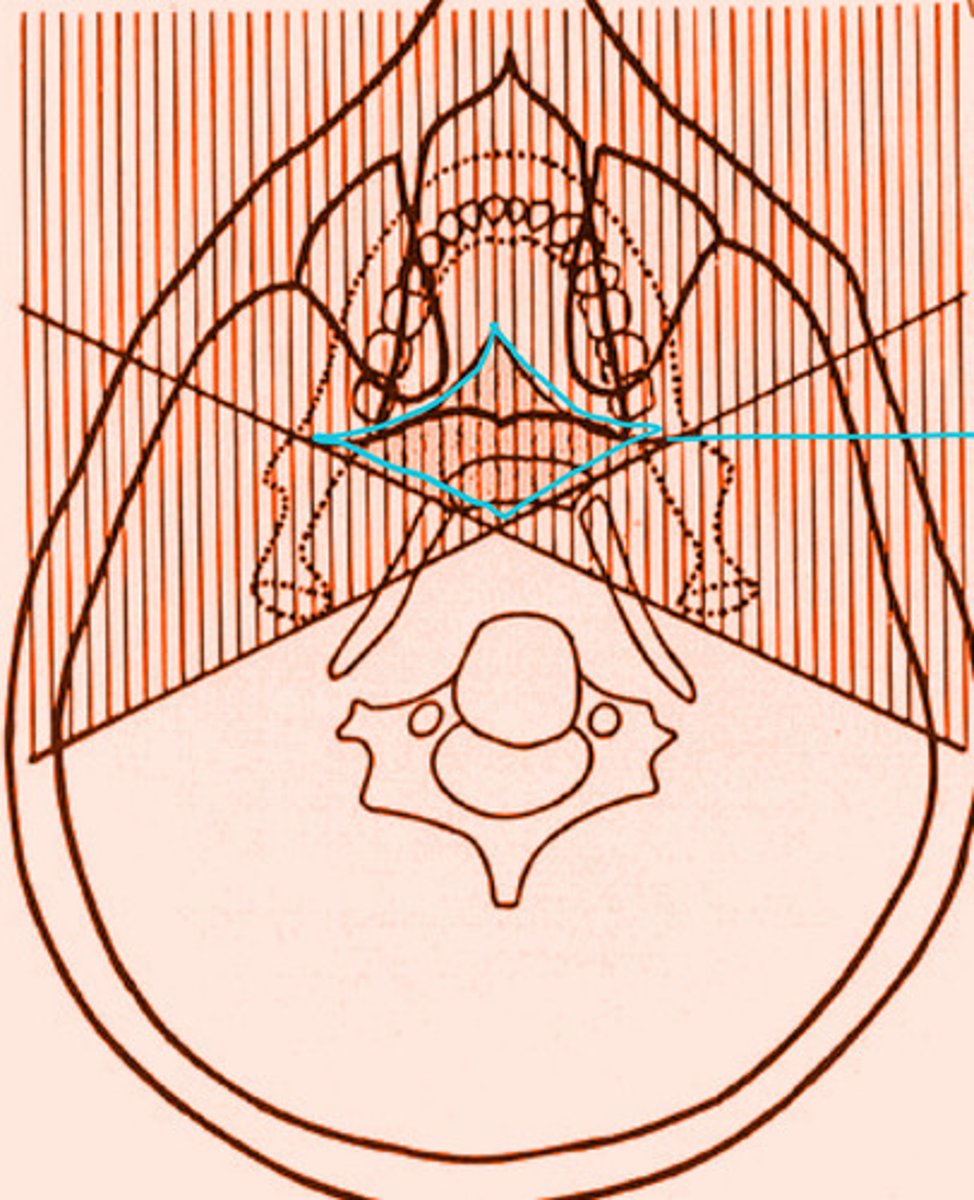

the shaded regions will produce what type of images?

ghost image/shadows

the shaded region within the blue diamond will produce a total of __ images

3

the shaded region within the blue diamond will produce a total of 3 images. What types of images are they?

2 real

1 ghost